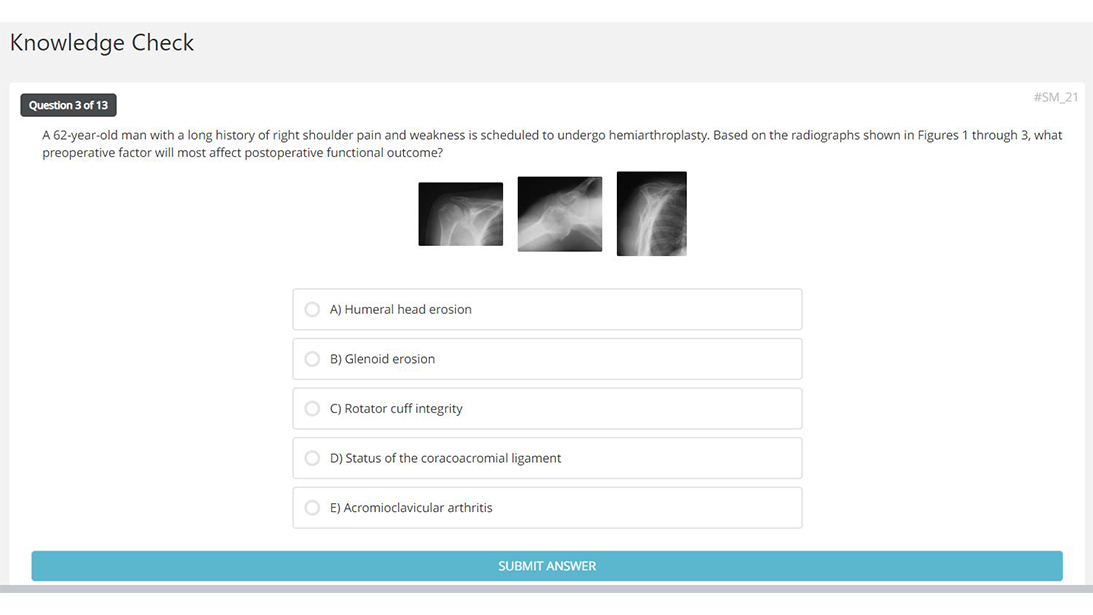

Sports Medicine of the Shoulder and Elbow

Course Director

Fotios Tjoumakaris, MD, FAAOS

Topics include: shoulder and elbow instability, SLAP lesions and proximal biceps pathology, shoulder arthritis in the young patient, and distal triceps and biceps ruptures.

50 CME Hours

5 Modules, 19 Lessons